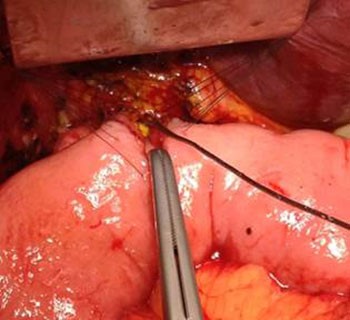

We also identified aberrant anatomy with the right posterior section duct of segment 6 draining directly into the common hepatic duct just above the biliary injury (Figure 3).

Figure 3. E1 biliary injury demonstrating the transected common bile duct with bakes dilator probes in the right posterior section duct and left hepatic duct orifices. The clipped distal common bile duct is also demonstrated.